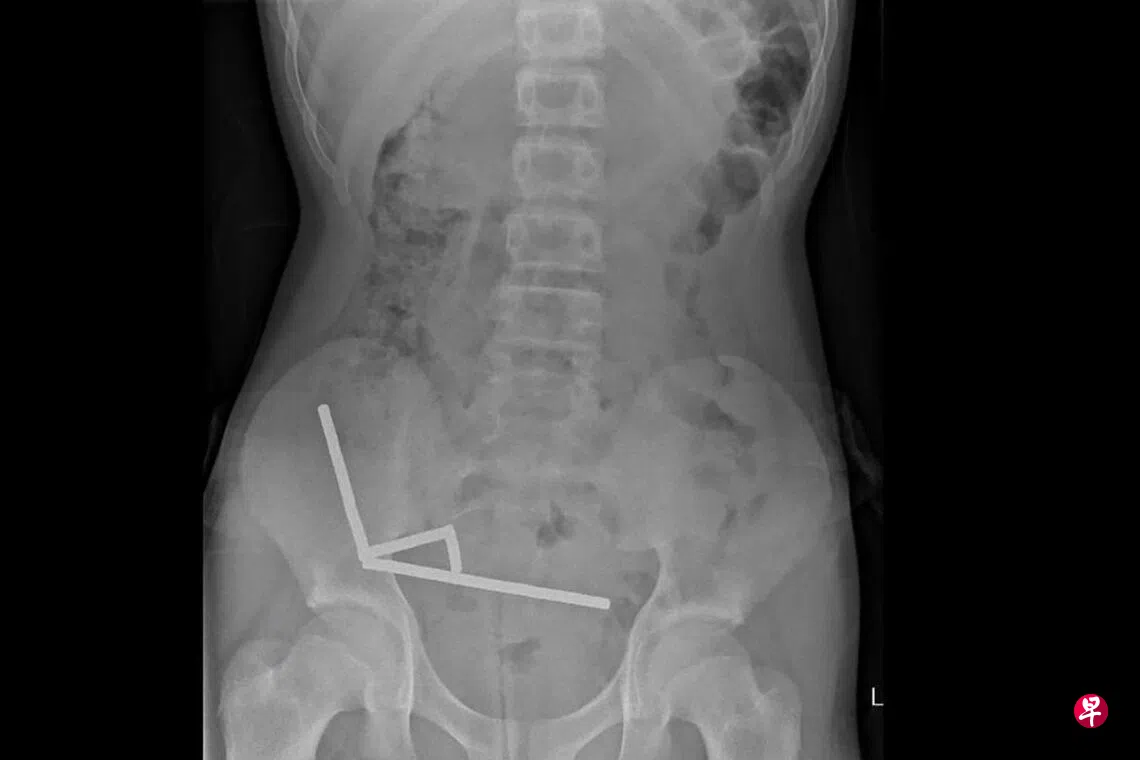

X光片显示在男童肠道里的钕铁硼磁铁黏连成四条直线。医生说:“这些磁铁似乎位于肠道里的不同区域,因为磁力作用而粘连在一起。”

医生说,钕铁硼磁铁的压力导致男童的小肠和盲肠的四个区域坏死。外科医生切除了坏死组织并取出磁铁。